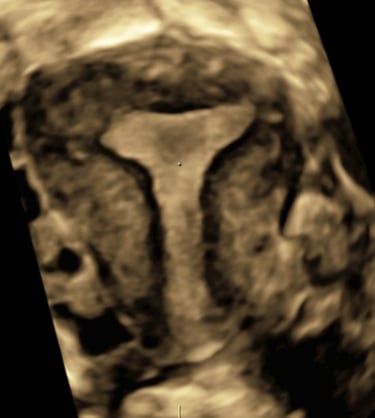

Lors d’une grossesse, l’échographie est un outil indispensable pour le suivi.

Il s’agit d’un examen de dépistage et non d’un diagnostic.